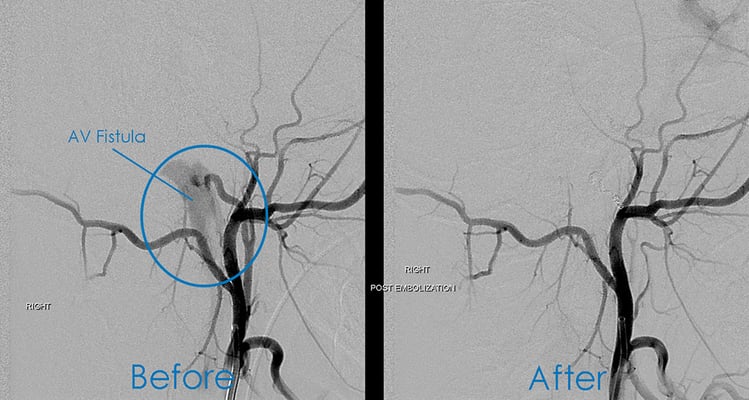

Toby was diagnosed with an arteriovenous (AV) fistula, which is an irregular, direct connection between an artery and a vein. These can occur anywhere in the body — Toby’s was in his brain, at the base of his skull behind his right ear.

With an AV fistula, somewhere along the path an artery or vein is damaged and a passageway is formed. This causes the blood to bypass the capillaries and flow directly from the artery to the vein. The ringing and whooshing sound Toby was hearing was actually the rush of blood flowing between the artery and vein.

The exam with Dr. Whelan was on a Friday. By the following Wednesday, Toby was at Children’s Wisconsin’s Neurosciences Center for surgery with Raphael Sacho, MD, a neurosurgeon and neurointerventionalist with special training in pediatric brain malformations. Over about two hours, Dr. Sacho made a small incision in Toby’s groin and threaded a thin, flexible tube up an artery to the base of Toby’s skull. A small metal coil was tightened around the fistula until the flow of blood was stopped.